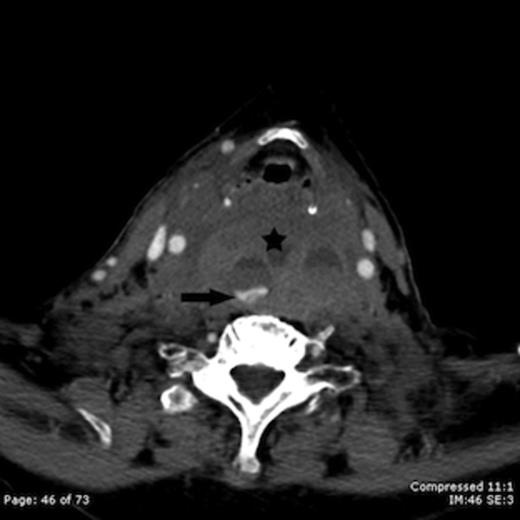

Computed tomography (CT) of the brain, neck and chest was performed. A massive retropharyngeal haematoma was observed extending between C2 and T4 vertebral body levels with displacement and compression of the trachea (Figure 1,2). There was no evidence of carotid, vertebral or internal jugular vein injury and no cervical fracture.

Contrast enhanced axial CT image taken at the level of the hyoid bone shows a large retropharyngeal haematoma (star) with active intravenous contrast extravasation (arrow)